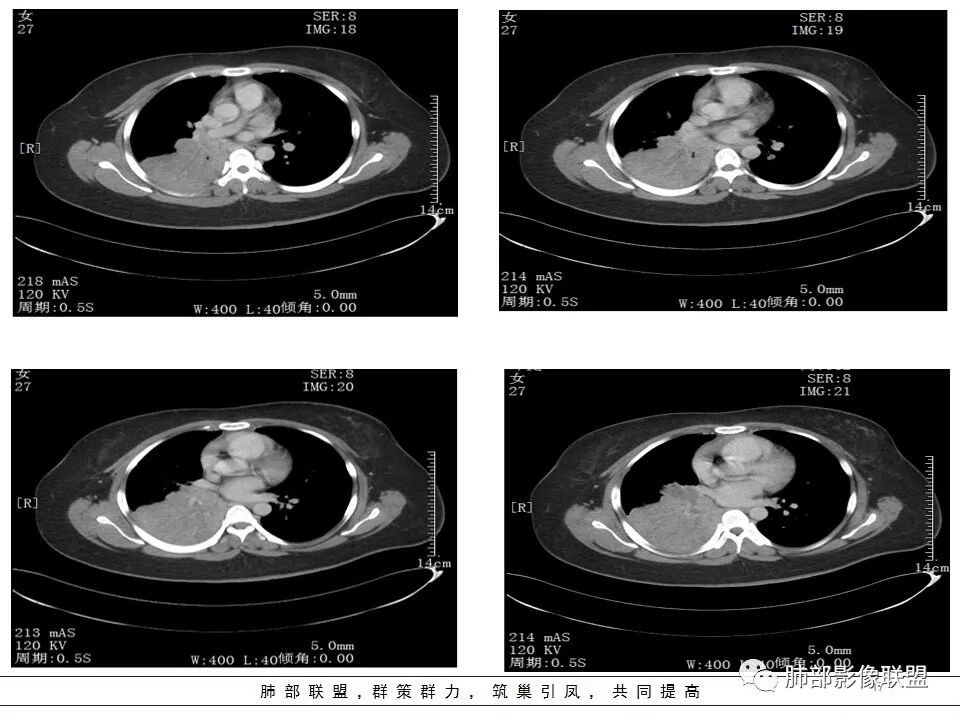

joyzhy :

右下肺门不规则结节强化,并远端支气管粘液栓及大片实变,实变边缘叶间裂膨隆,考虑支气管占位并阻塞性肺炎,涎腺类恶性肿瘤(粘液表)需要鉴别。

右中间支气管阻塞,右肺下叶实变,未见明显支气管空气征,增强中间支气管内病变未见明显强化,纵隔淋巴结增大,偏向恶性病变,结合病史,青年人,肿瘤性病变,支气管表皮样粘液癌可能。

右中间及右下叶支气管堵塞,右下肺不张,下叶堵塞支气管近端见结节状略高密度,远端见管状低密度,堵塞常见原因:结核、肿瘤、异物。强化不明显,粘液表皮样癌?结核?建议支气管镜进一步检查。

年轻女性,右肺下叶支气管堵塞伴不张,增强轻度强化,血管走形自然,右肺门区见强化结节影,支气管来源肿瘤伴不张。不张软组织影跨右肺中叶及下叶,需鉴别纤维瘤。

生来征服~浪子 :

右下肺大片实变影,近肺门处明显膨隆,远端可见粘液栓形成。纵隔多发肿大淋巴结。增强扫描可见血管造影征,血管边缘欠光整。考虑肿瘤。

患者青年女性,发热6 天,咳嗽、咳痰3天。为黄脓痰。胸部CT:右肺体积稍小,右中间支气管肿物堵塞,中叶、下叶大片实变不张,与正常肺组织分界清楚。增强实变影明显强化,右下肺支气管近心端见类圆形强化结节影,血管纤细,部分支气管显影变细,纵隔淋巴结肿大。结合无呼吸困难症状,病程长。综合考虑低度恶性病变并阻塞性肺炎,类癌可能大,鉴别结核、淋巴瘤。

右肺中下叶实变伴气管腔内粘液栓形成,肺门区见不规则软组织肿块,气管腔狭窄,截断,呈中等强化,纵膈内肿大淋巴结,考虑气管腔内原发肿瘤性病变伴肺实变

右肺体积缩小,右肺巨大低密度肿块并下叶不张,无胸膜尾征,定位肺内,右中间支气管堵塞,肿块内可见粘液栓,不均匀强化,其内血管走行自然,右下肺受侵边缘不整,纵隔内淋巴结肿大,考虑为恶性,年轻女性,粘液表皮样癌首选,其次肉瘤或类癌。